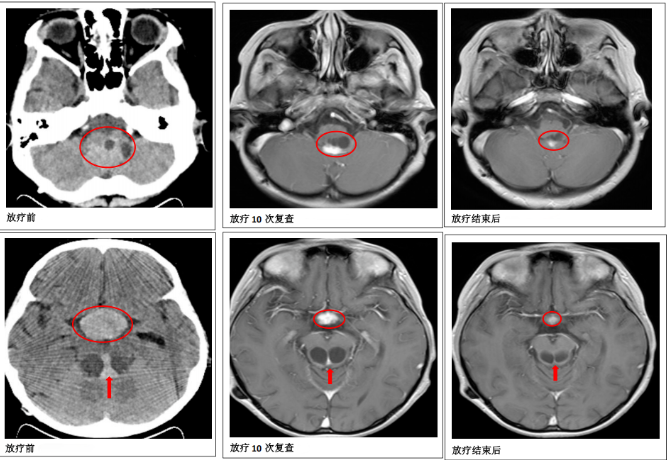

放疗10次后,医生再次给患儿做了颅脑核磁共振检查,和之前的检查结果对比发现,颅内的肿瘤明显缩小了,说明治疗效果很好,对放疗敏感,临床可以诊断为颅内生殖细胞肿瘤,可按颅内生殖细胞肿瘤的放疗计划继续放疗。为了减少放疗可能带来的副作用,肿瘤科一病区放疗医师根据新的检查结果重新调整了放疗方案,这样既能有效控制肿瘤,又能减少对患儿的伤害。